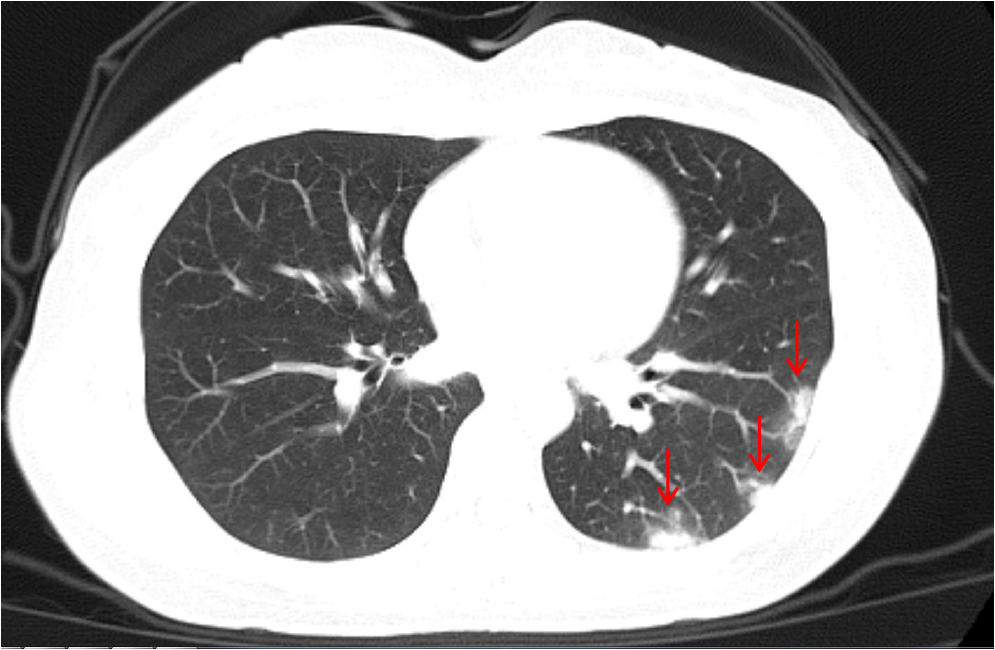

目前看来,COVID-19除了导致典型的严重呼吸性障碍综合症,亦可表现为流感类轻型症状以及无症状感染。冯友军课题组通过合作研究发现这批意大利的输入病例无发烧症状,仅仅表现为咳嗽。胸部CT扫描显示有不同程度的磨玻璃样浑浊,系病毒感染的典型特征 (图3)。在此之前,该课题组在丽水当地患者中就发现了流感类症状的COVID-19携带者通过聚集性接触 (如就餐) 可导致受传染者重症肺炎的产生,相关结果已在PrePrint预印本平台发布。

图3:流感类症状的COVID-19病人的肺部CT检测特征